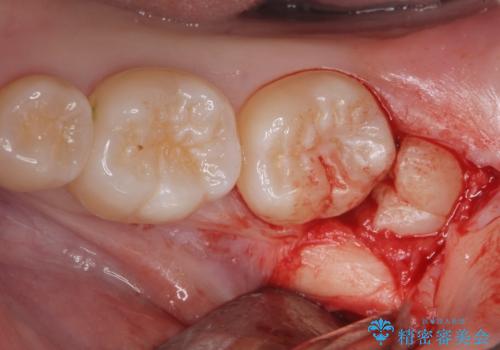

- 左上下親知らず抜きたいとの事で来院。

レントゲン、CTを撮影し安全を考慮して抜歯術を行いました。

無事に親知らず抜歯ができました。